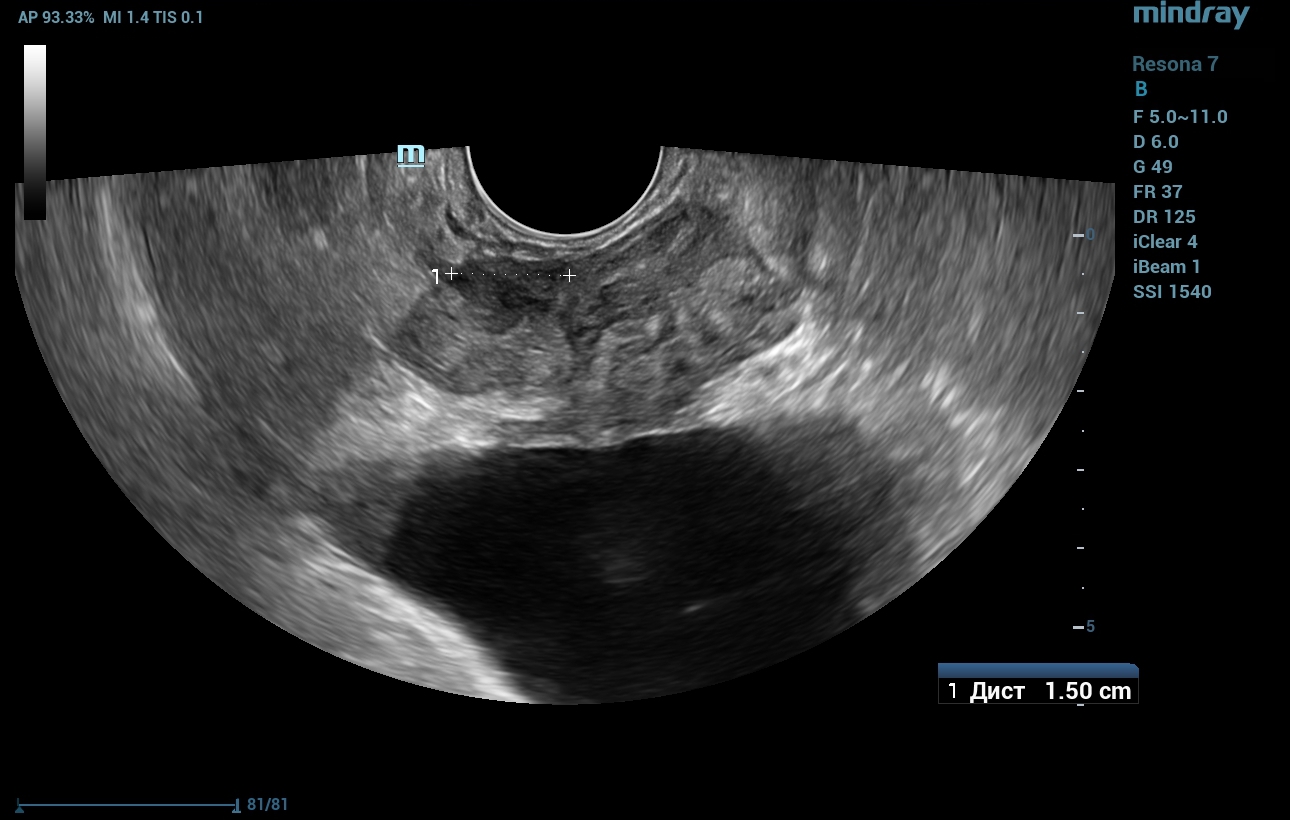

A transrectal ultrasound examination (TRUS) was performed on the Resona 7 ultrasound machine (Mindray, China). The volume of the prostate gland measured 36 ml, and a hypoechoic lesion of indistinct, uneven contour with a maximum diameter of 15 mm was seen in the peripheral zone of the right lobe, near the interlobular furrow (Fig. 1).